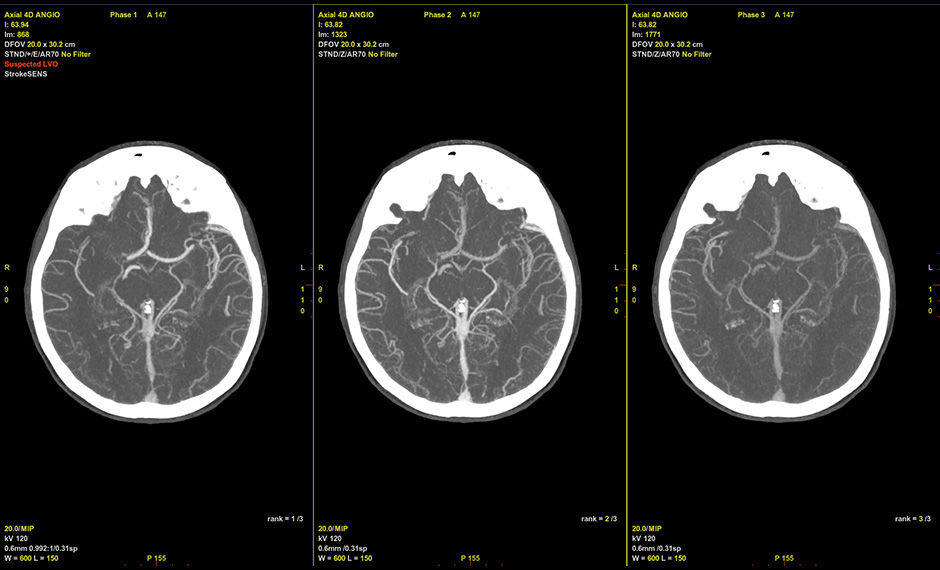

CT-Angiographie

Zeigt CTA-Bilder automatisch in einer dicken 2D-MIP-Ansicht mit optimierten WW/WL-Einstellungen an.

Umfasst die automatisierte LVO-Erkennung und -Meldung von StrokeSENS.1

Passt sich intelligent an Ihre Scanverfahren an und synchronisiert bis zu sechs mehrstufige CTA-Durchläufe und ermöglicht so eine dynamische Bewertung des kollateralen Blutkreislaufes.